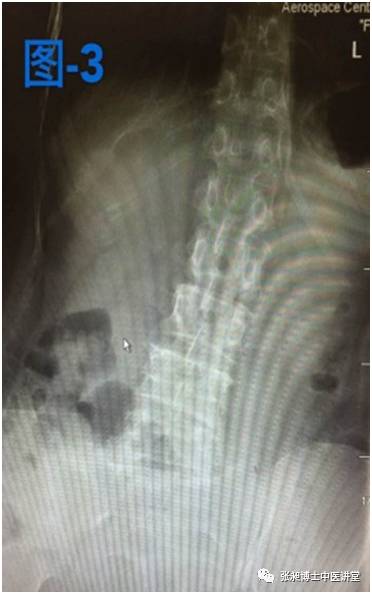

当时这位阿姨主要临床表现:腰痛,伴右下肢大腿外侧疼痛,疼痛不过膝盖。右侧臀部疼痛,范围局限,右侧强迫体位,无法弯腰,弯腰时右侧腰部酸痛。下图是当时做的影像学检查。患者很是痛苦,腰椎侧弯已经严重影响患者生活。张昶医生建议患者小针刀治疗。

后来这位患者经过两个月的小针刀治疗后疼痛缓解,右侧强迫体位缓解,生活质量也得到很大提高。腰椎侧弯也好转,如下图所示,是患者治疗前和治疗后的对比。